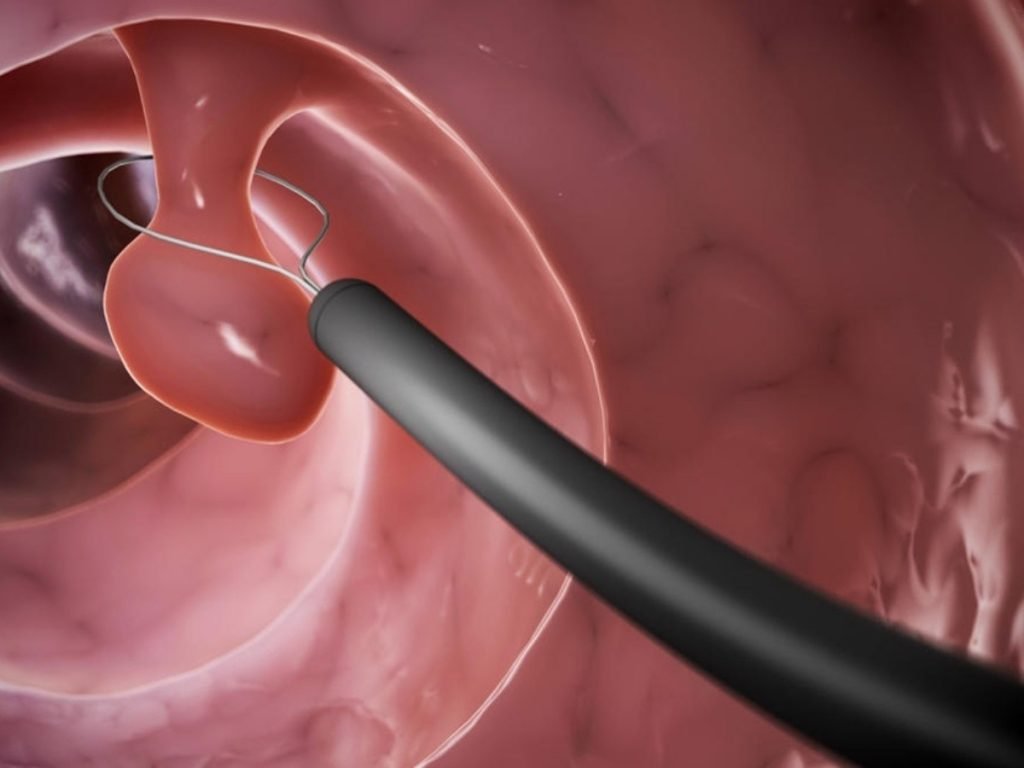

Quando indicado tratamento cirúrgico, a histeroscopia (na fotografia abaixo e à direita, o pólipo endometrial está representado pela letra “P”) é o método de escolha e pode ser realizada até mesmo em ambiente ambulatorial para pólipos pequenos. O tratamento dos pólipos endometriais maiores, contudo, requer internação hospitalar e abordagem em centro cirúrgico, com a devida anestesia.